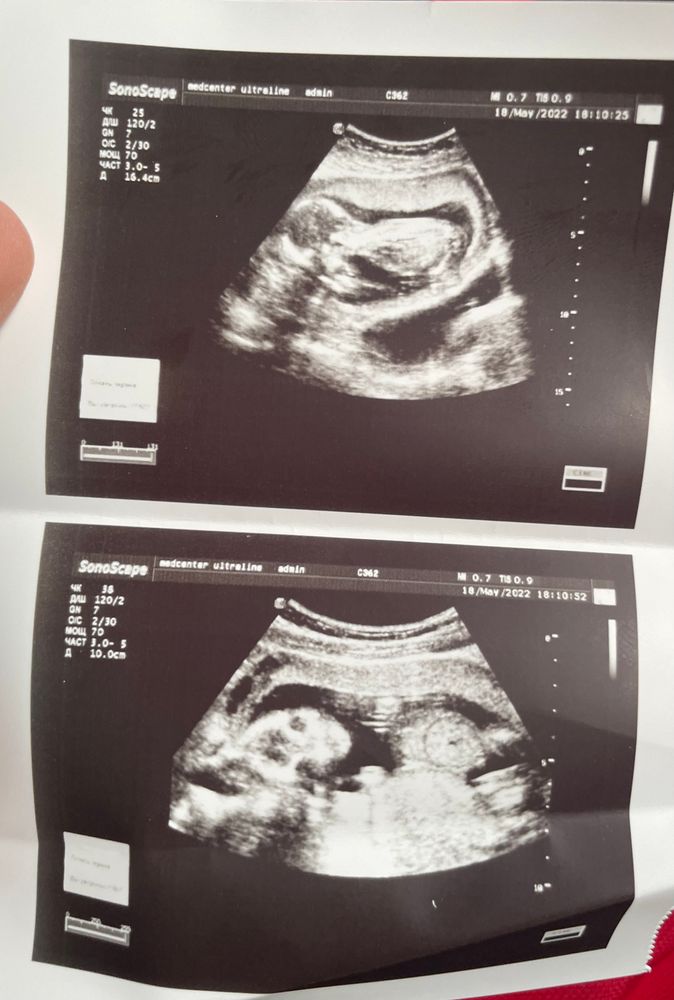

Всем добрый день! Сходила на узи 17 недель, пол не сказали. Но есть снимок. Возможно ли тут что нибудь разглядеть?

но прямо такая лапатулька красивая, что хочется сказать девочка. Но это уже пальцем в небо. Прелесть малютка! Не переживайте, не за горами 2 скрининг.